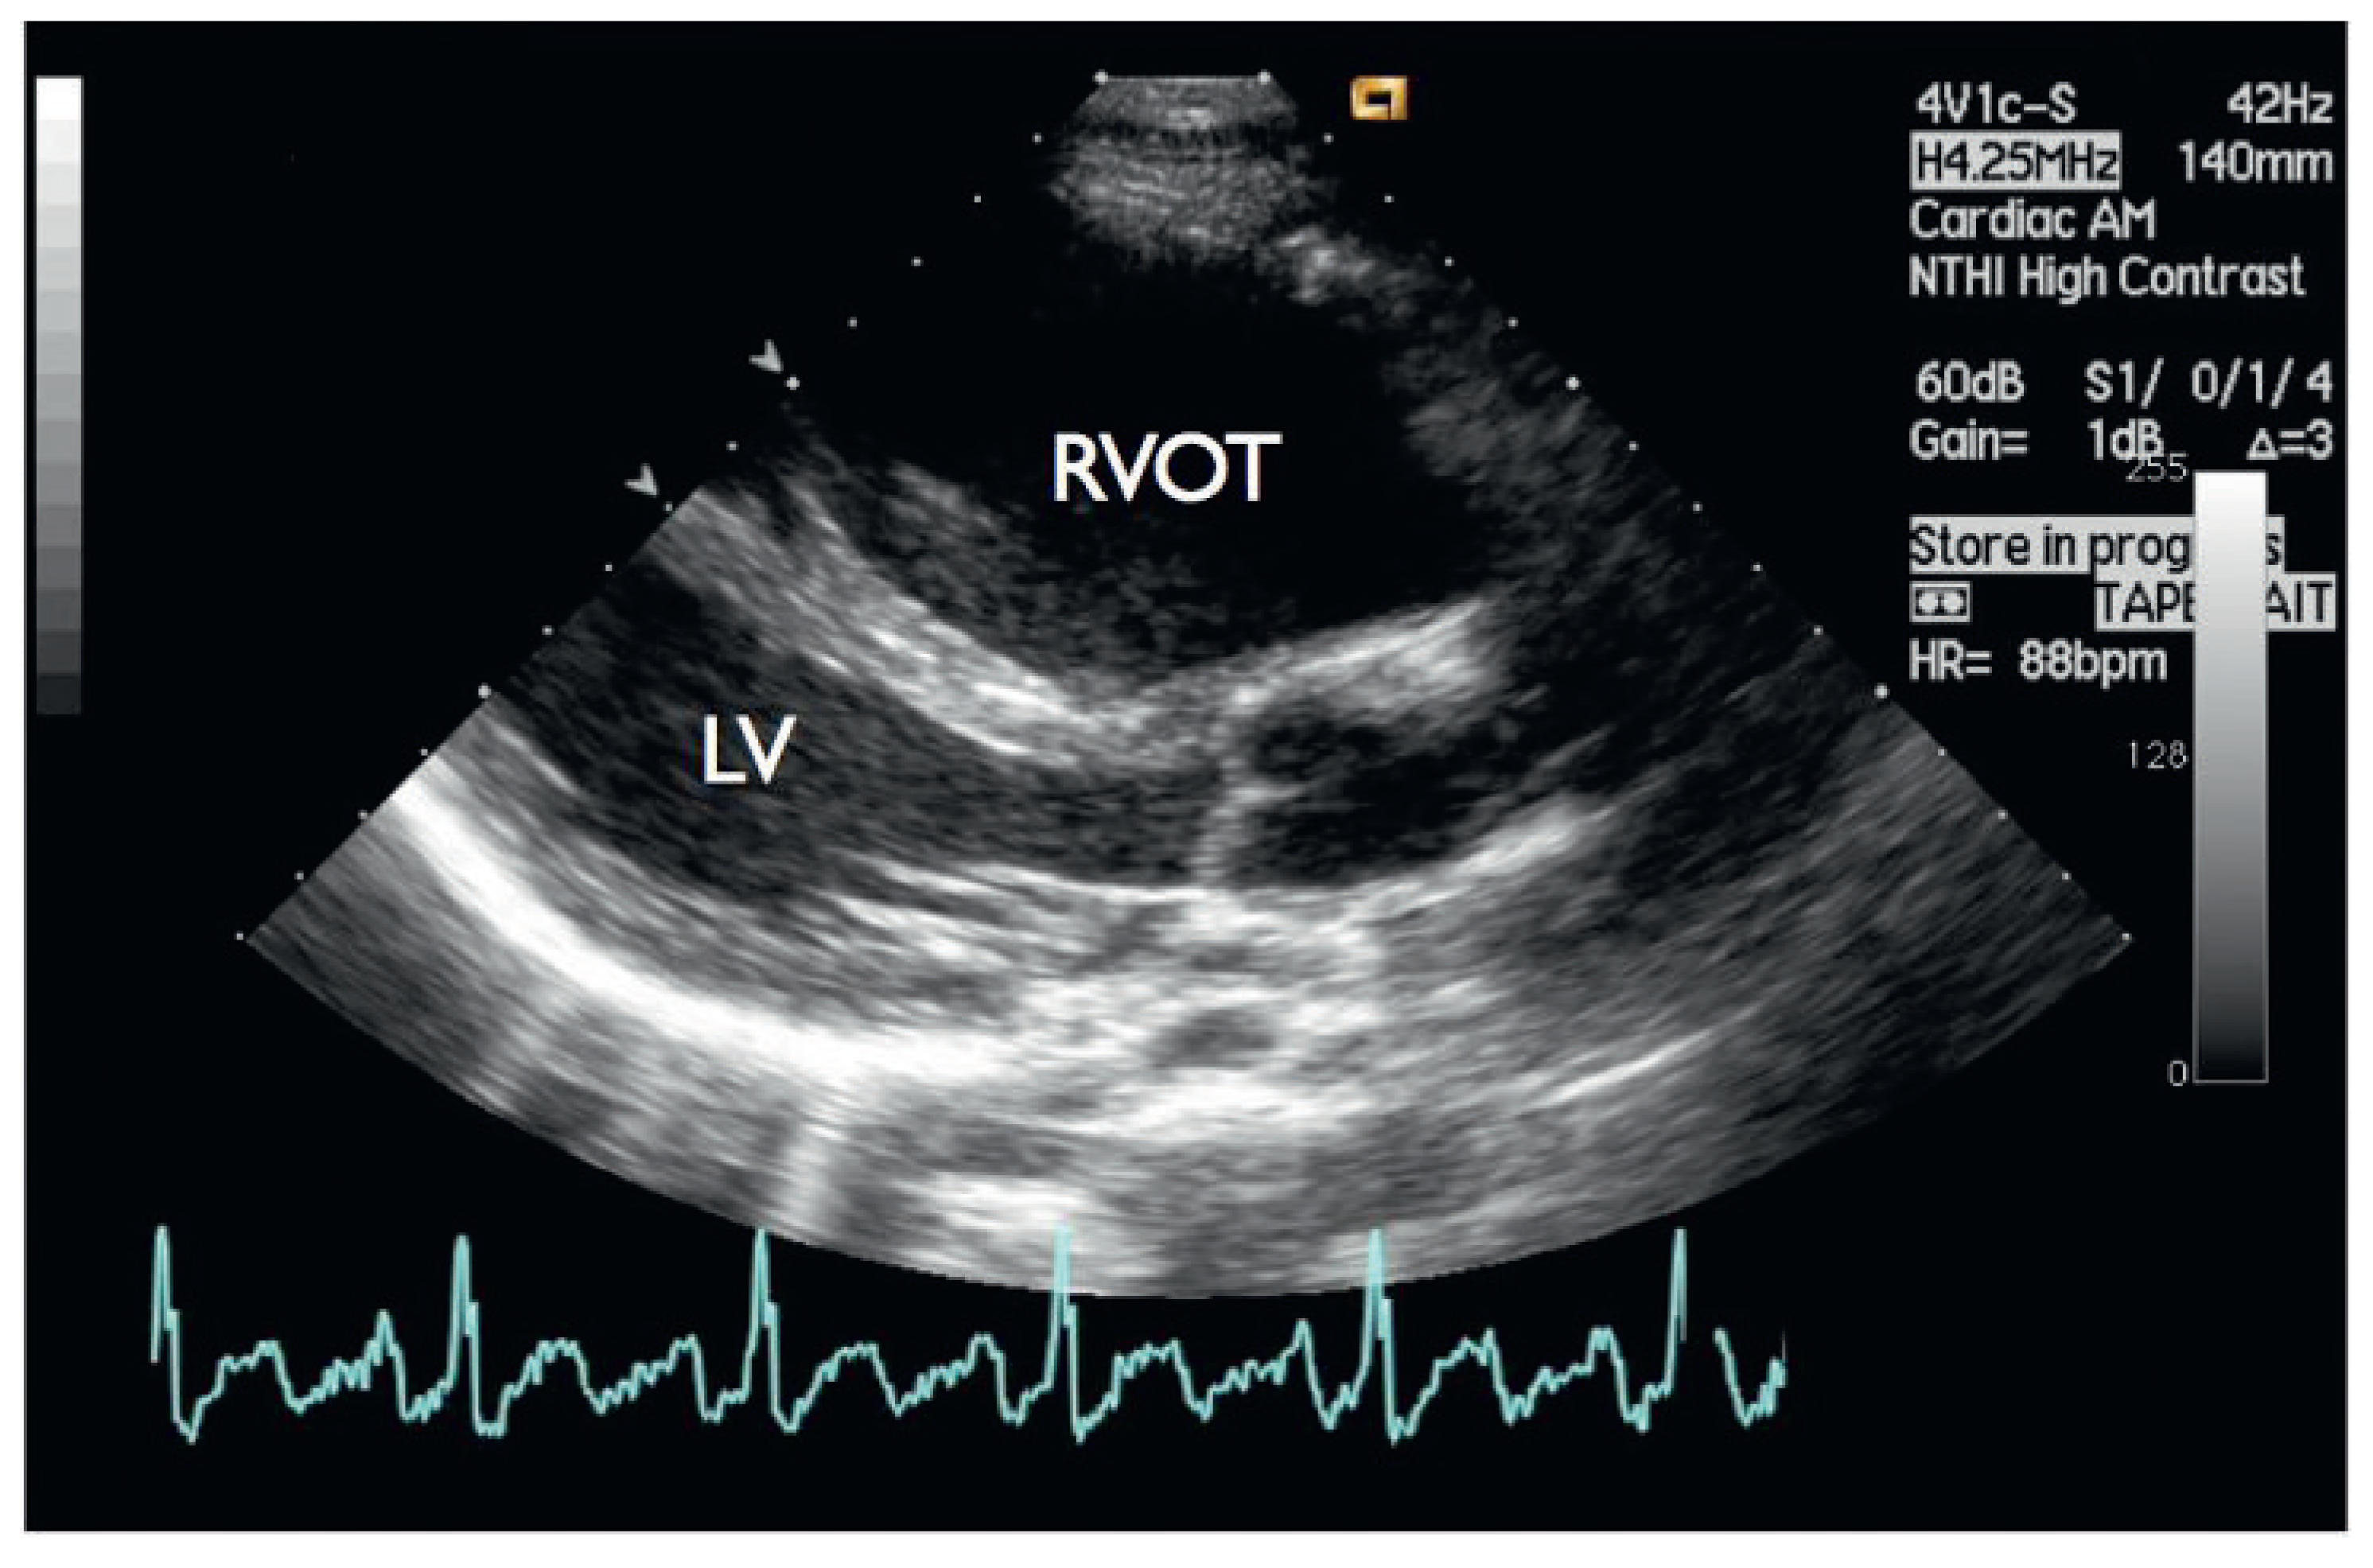

Typical Signs of Secundum Atrial Septal Defect in a Young Man

Case report